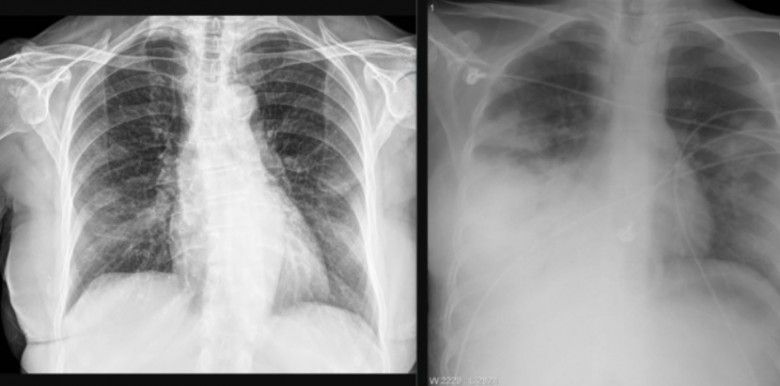

Foto: Ilustrasi Pneumonia (Merdeka.com)